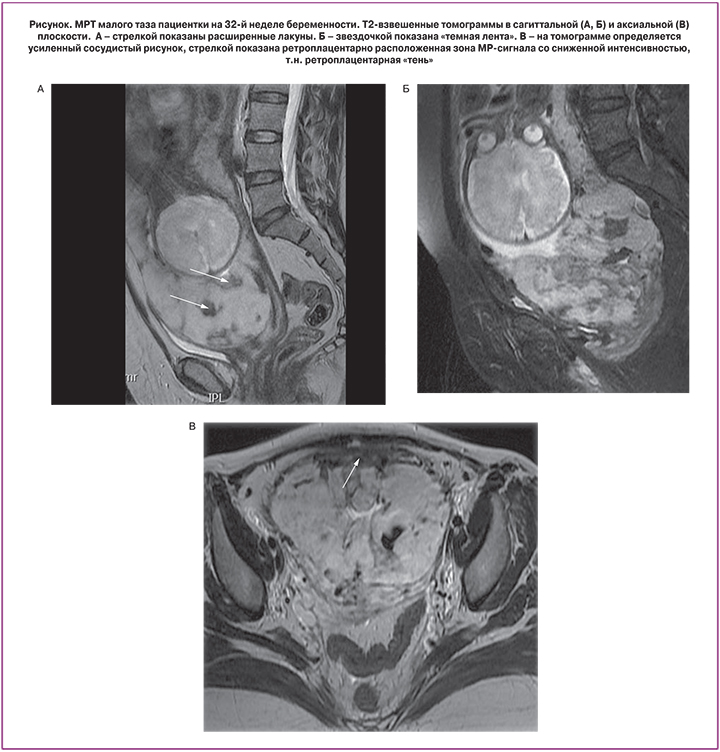

Непосредственный анализ характерных МР-признаков врастания плаценты показал, что абсолютно во всех случаях определялась неоднородность структуры плаценты наряду с усилением ее сосудистого рисунка (табл. 2). С одинаковой частотой (90%) определялась ретроплацентарная «тень» (рисунок). Однако в 1-й группе наиболее часто определялись единичные лакуны (70%), в то время как их множественный характер был представлены лишь в одном случае (10%), что имеет статистически значимую разницу по сравнению со 2-й группой, где характерную картину «швейцарского сыра» наблюдали в половине случаев (p=0,0321). ОШ placenta increta при выявлении множественных лакун составило 9,0 (95% ДИ 1,0; 85,0). Темные полосы в структуре плаценты в 5,7 раза чаще определялись также в группе с более глубокой степенью врастания плаценты (95% ДИ 1,0; 32,4). Стоит отметить, что одновременное сочетание данного признака с множественными лакунами и центральным предлежанием плаценты показал 100% специфичность в определении placenta increta и такой же высокий показатель характеризовал placenta accreta при полном исключении данных маркеров. Статистически не имели значимого различия такие признаки, как истончение миометрия (р=0,3006), выбухание стенки матки (р=0,2733), а также шеечно-треугольниковая сосудистая гиперплазия (0,7602). Отдельно стоит отметить, что абсолютно во всех случаях, в том числе с верифицированным вариантом placenta percreta, не выявлено хорошо визуализируемого прорастания плаценты в смежные с маткой органы.

Наряду с этим у большинства исследуемых больных определялась изоинтенсивная, так называемая ретроплацентарная «тень» в проекции серозного покрова матки в непосредственном локусе врастания. Данный признак изначально определялся при УЗИ и обусловлен отсутствием миометрия и неоваскуляризацией между задней стенкой мочевого пузыря и передней стенкой матки [14]. На МРТ данный признак определяется как зона гипоинтенсивного МР-сигнала на Т2ВИ. С позиции эффективного междисциплинарного взаимодействия мы оставили название этого признака без изменений. Шеечно-треугольниковая гиперплазия является мало изученным признаком, и в данной работе не наблюдалось значимой разницы в группах. Другой критерий, показывающий выраженность сосудистого компонента – это наличие «темных лент», которые значительно чаще встречаются при placenta increta. Несмотря на то, что природа их происхождения до сих пор не раскрыта, высказываются предположения, что морфологический субстрат составляют отложения фибрина или участки фиброзной ткани, образовавшиеся на месте гематомы [15, 16]. Данное предположение согласуется с выявленной закономерностью и подтверждает патогенетически более агрессивный характер инвазии placenta increta по сравнению с accretа. Особого внимания заслуживают лакуны, которые также являются специфическим маркером врастания. Они формируются вторично за счет высокоскоростного кровотока из радиальных и аркуатных артерий (пиковая систолическая скорость часто >10 см/с) [17]. Их множественный характер проявляется по мере увеличения степени прорастания ворсин, что опять же подтверждает ранее высказанную теорию: чем сильнее выражены нарушения сосудистой гистоархитектоники, тем глубже инвазия плаценты.